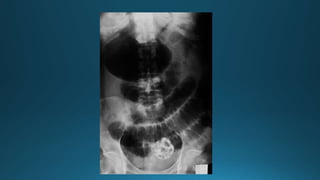

Diagnóstico Íleo mecánico uobstructivo Estudio de Imágenes -Radiografías Radiografía Simple de abdomen -Asas de intestino delgado dilatadas en la parte proximal a la obstrucción y disminución de aire en la zona distal a ésta. -Niveles Hidroaéreos(decúbito lateral con rayo horizontal) -Aire libre sudiafragmático indica perforación intestinal

• 13.

Vólvulo de sigma.La Rx simple de abdomen muestra el típico signo del “grano de café”.